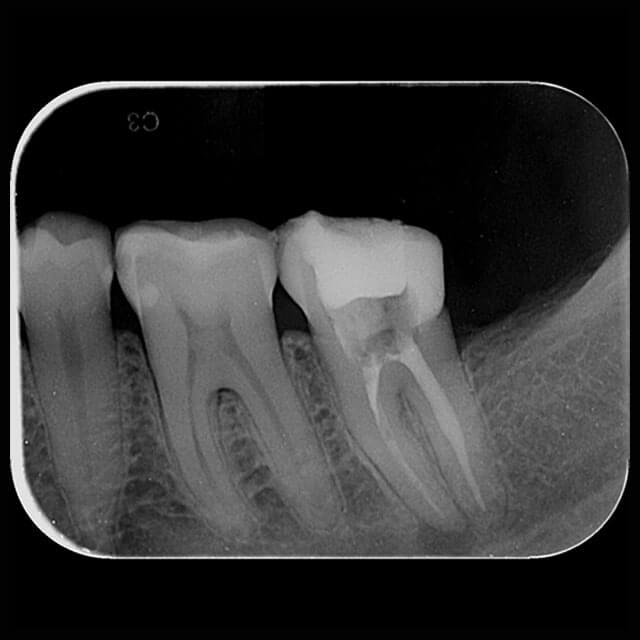

Radiografia Periapical

A radiografia periapical ou RX periapical é um exame utilizado para mostrar radiograficamente a anatomia de um ou mais dentes (desde a coroa ao final da raiz), assim como as estruturas anatômicas vizinhas, ou seja, que estão ao redor dos dentes.

Esta radiografia pode ser usada para estudar qualquer dente (molar, pré-molar, e incisive os caninos) seja na arcada dentária superior ou na inferior para fins de diagnóstico e tratamento.